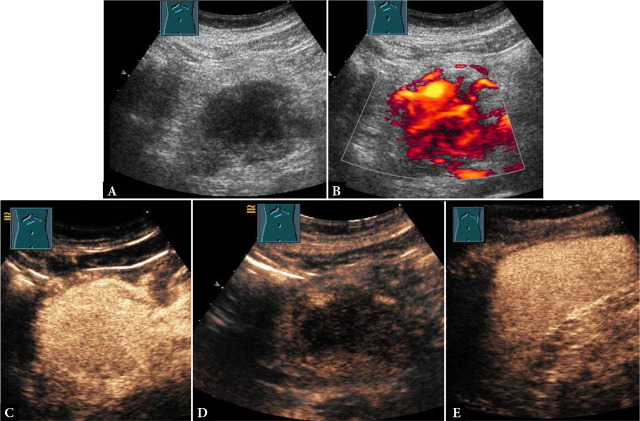

Presentation of extramedullary myeloma manifestations on B-mode (B-US) and contrast-enhanced ultrasound (CEUS).

Results: In most cases, extramedullary myeloma manifestations were located in the chest wall (n = 11; 45.8%). In all 24 cases, extramedullary myeloma manifestations were hypoechoic on B-mode ultrasound. N = 16 (66.6%) of extramedullary myeloma manifestations had smooth and n = 8 (33.3%) had irregular borders. The mean lesion size was 5.4 cm. On contrast-enhanced ultrasound, extramedullary myeloma manifestations presented arterial hyper- (n = 20; 83.3%) or isoenhancement (n = 4; 16.7%) followed by parenchymal iso- (n = 1; 4.2%) or hypoenhancement (n = 23; 95.8%). In molecular genetic analysis, every patient with reliable FISH results tested positive for at least one aberration considered "high-risk".

Conclusion: Extramedullary myeloma manifestations were typically hypoechoic on B-mode ultrasound. On contrast-enhanced ultrasound, they presented characteristic arterial hyperenhancement followed by parenchymal washout. All patients studied for the genetic risk status were found to be "high-risk".